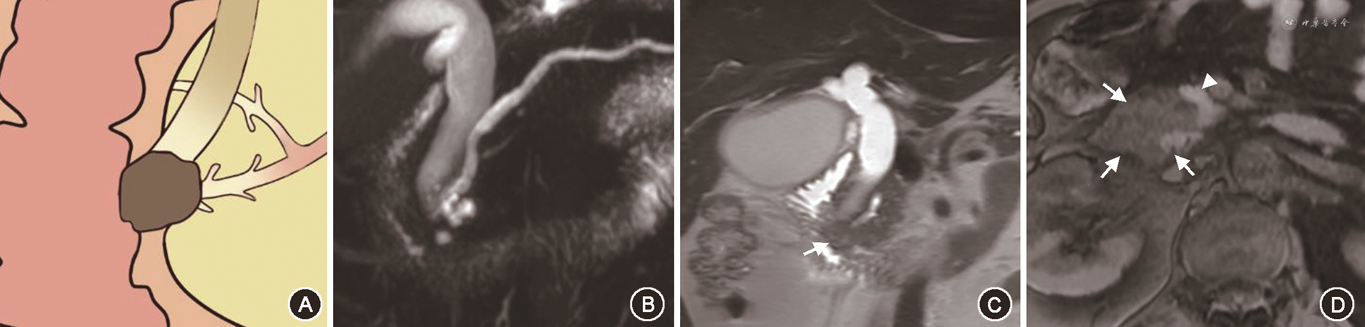

在对有意义单因素指标的分析中,笔者将PAC的MRI征象进行总结,最后归纳为十二指肠乳头结节型、胰腺肿块型、胆总管壁增厚型、壶腹部肿块型及胆总管腔内结节型5种表现类型。十二指肠乳头结节型MRI征象为位于十二指肠腔内的病灶,多为等信号,在十二指肠乳头形成突入腔内的结节,MRCP上胆总管及胰管扩张呈双管征,胰胆管角度较小,双管征走行呈平行或聚拢(图1)。胰腺肿块型MRI征象为胰腺内低信号肿块,MRCP上胆总管及胰管单独或同时狭窄截断可分别出现双管征、三管征、四管征,截断胰管周围可见扩张侧支,肿块引起胰胆管角度增大,管征呈分离走行(图2)。胆总管壁增厚型MRI征象为胆总管远段管壁增厚,近段胆管扩张,MRCP上胰管较少扩张,近段扩张胆管、梗阻下方远段胆总管与胰管呈三管征(图3)。壶腹部肿块型在MRI图像上表现为壶腹部跨壁生长的肿块,可与胰腺、十二指肠肠壁分界不清,但较少使十二指肠乳头表现为结节型,MRCP管征多为双管征(图4)。胆总管腔内结节型在MRCP图像上远端胆总管内见结节样充盈缺损伴胆道梗阻,远段胆总管、近段扩张胆总管及胰管呈三管征(图5)。

Fisher精确概率法结果显示,IPAC与PPAC在MRI影像5分型的差异具有统计学意义(P<0.001)(表4)。经调整检验水准后的 Bonferroni 法两两比较结果显示,十二指肠乳头结节型与胰腺肿块型、胆总管壁增厚型及壶腹部肿块型的差异均具有统计学意义(均P<0.005)。IPAC多表现为十二指肠乳头结节型(15/21,71.4%)(图1),PPAC更多表现为胰腺肿块型(18/38,47.4%)、胆总管壁增厚型(9/38,23.7%)或壶腹部肿块型(9/38,23.7%)(图2, 3, 4),IPAC(2/21,9.5%)与PPAC(0,0)均较少表现为胆总管腔内结节型(图5)。

IPAC和PPAC在MRI图像上均较少表现为胆总管腔内结节型,本研究中2例胆总管腔内结节型均为IPAC,但样本量较少,此分型在PAC两种组织学亚型间的差异无统计学意义。但需要注意的是,MRI胆总管腔内结节型仅包括病灶完全位于胆总管内的结节,未包括在胆总管远端形成结节样凸缘的其他来源肿块。